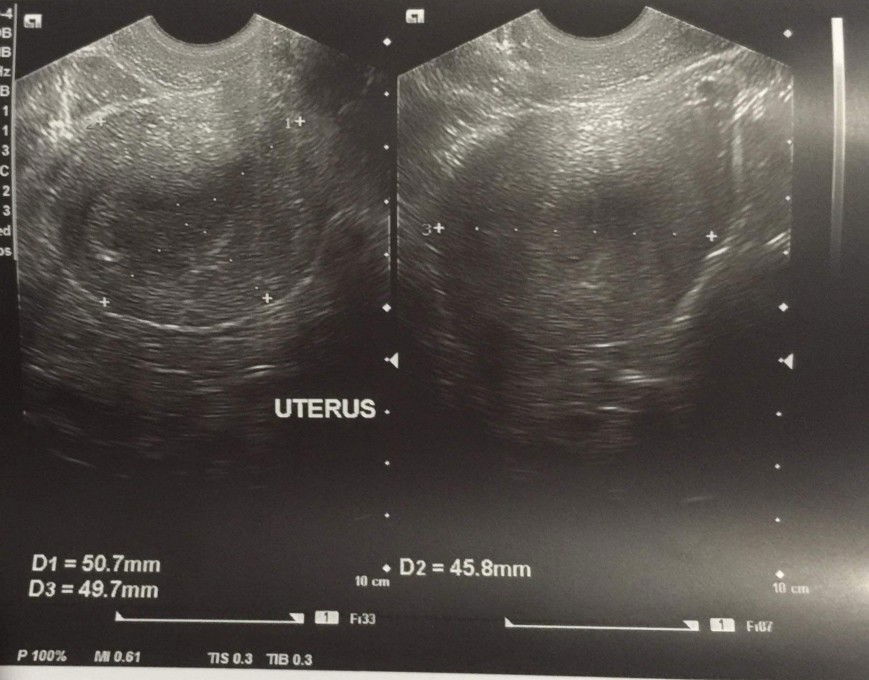

6weeks preggy

..March 16 morning positive 2 pt. May pain side ng puson sobra sakit at nag pa er. March 16 8pm spotting 3days yun bed rest. Take duvadilan that night n nex morning. Nag txt sa ob req TVS March 17 TVS done. Wala GS sac wala pa heartbeat baby pina stop duvadilan. BED REST March 20 2pm sumakit pusun parang pag nag mmens ako. Tapos bleeding flow panag pperiod. Till now March 21 morning (ready na) nag PT ulit kc nag wworry mens na itsura na blood. NEGATIVE na po 2 pt. Galing na dn ng ob failed pregnancy dw. ? Ps. march 20 night iniyak ko na lahat kc ramdam ko na wala na. Kc sa flow ng blood na lumlabas.

6weeks n 1 day

March 16 morning positive 2 pt. May pain side ng puson sobra sakit at nag pa er. March 16 8pm spotting 3days yun bed rest. Take duvadilan that night n nex morning. Nag txt sa ob req TVS March 17 TVS done. Wala GS sac wala pa heartbeat baby pina stop duvadilan. BED REST March 20 2pm sumakit pusun parang pag nag mmens ako. Tapos bleeding flow panag pperiod. Till now March 21 morning (ready na) nag PT ulit kc nag wworry mens na itsura na blood. NEGATIVE na po 2 pt. Galing na dn ng ob failed pregnancy dw. ? Ps. march 20 night iniyak ko na lahat kc ramdam ko na wala na. Kc sa flow ng blood na lumlabas.

6weeks pregnant today

Mejo natatakot ako nag pa ultrasound tapos wala makita Gestational Sac. Baka dw early pregnancy. Pls pray for me n my baby